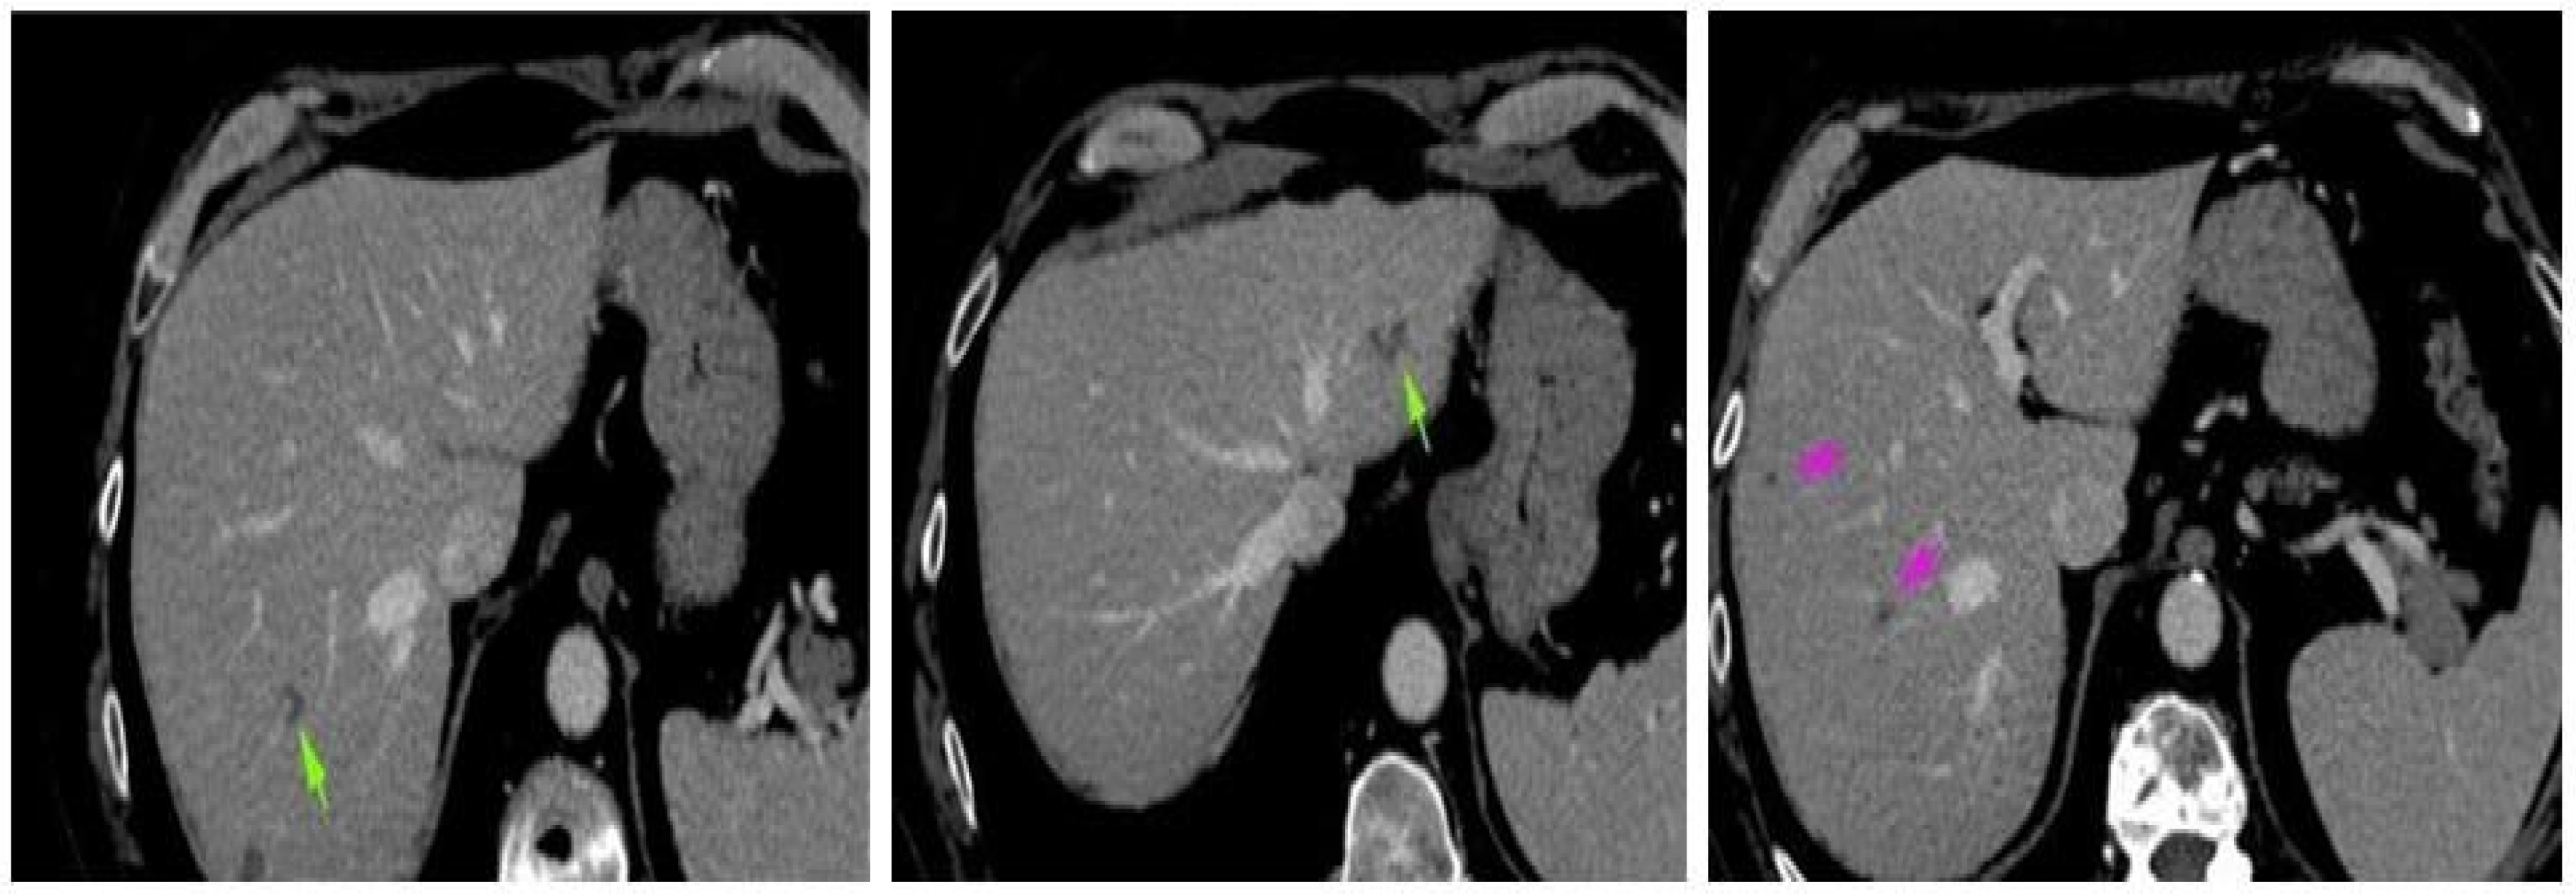

2. Case Presentation